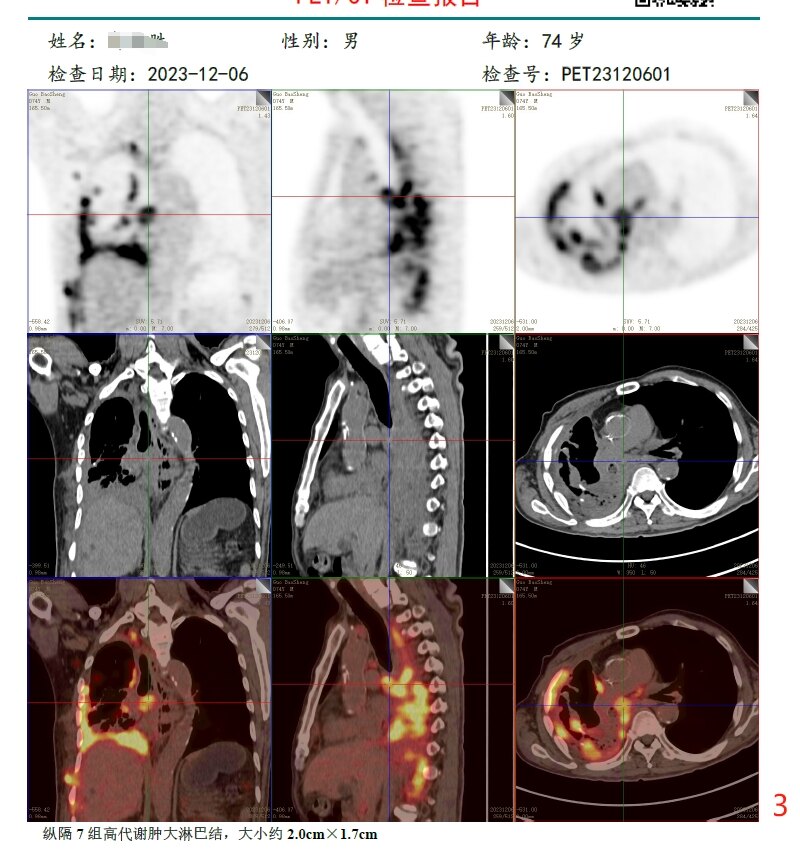

放疗前PET/CT(2023-12-06):

病变层面:

3